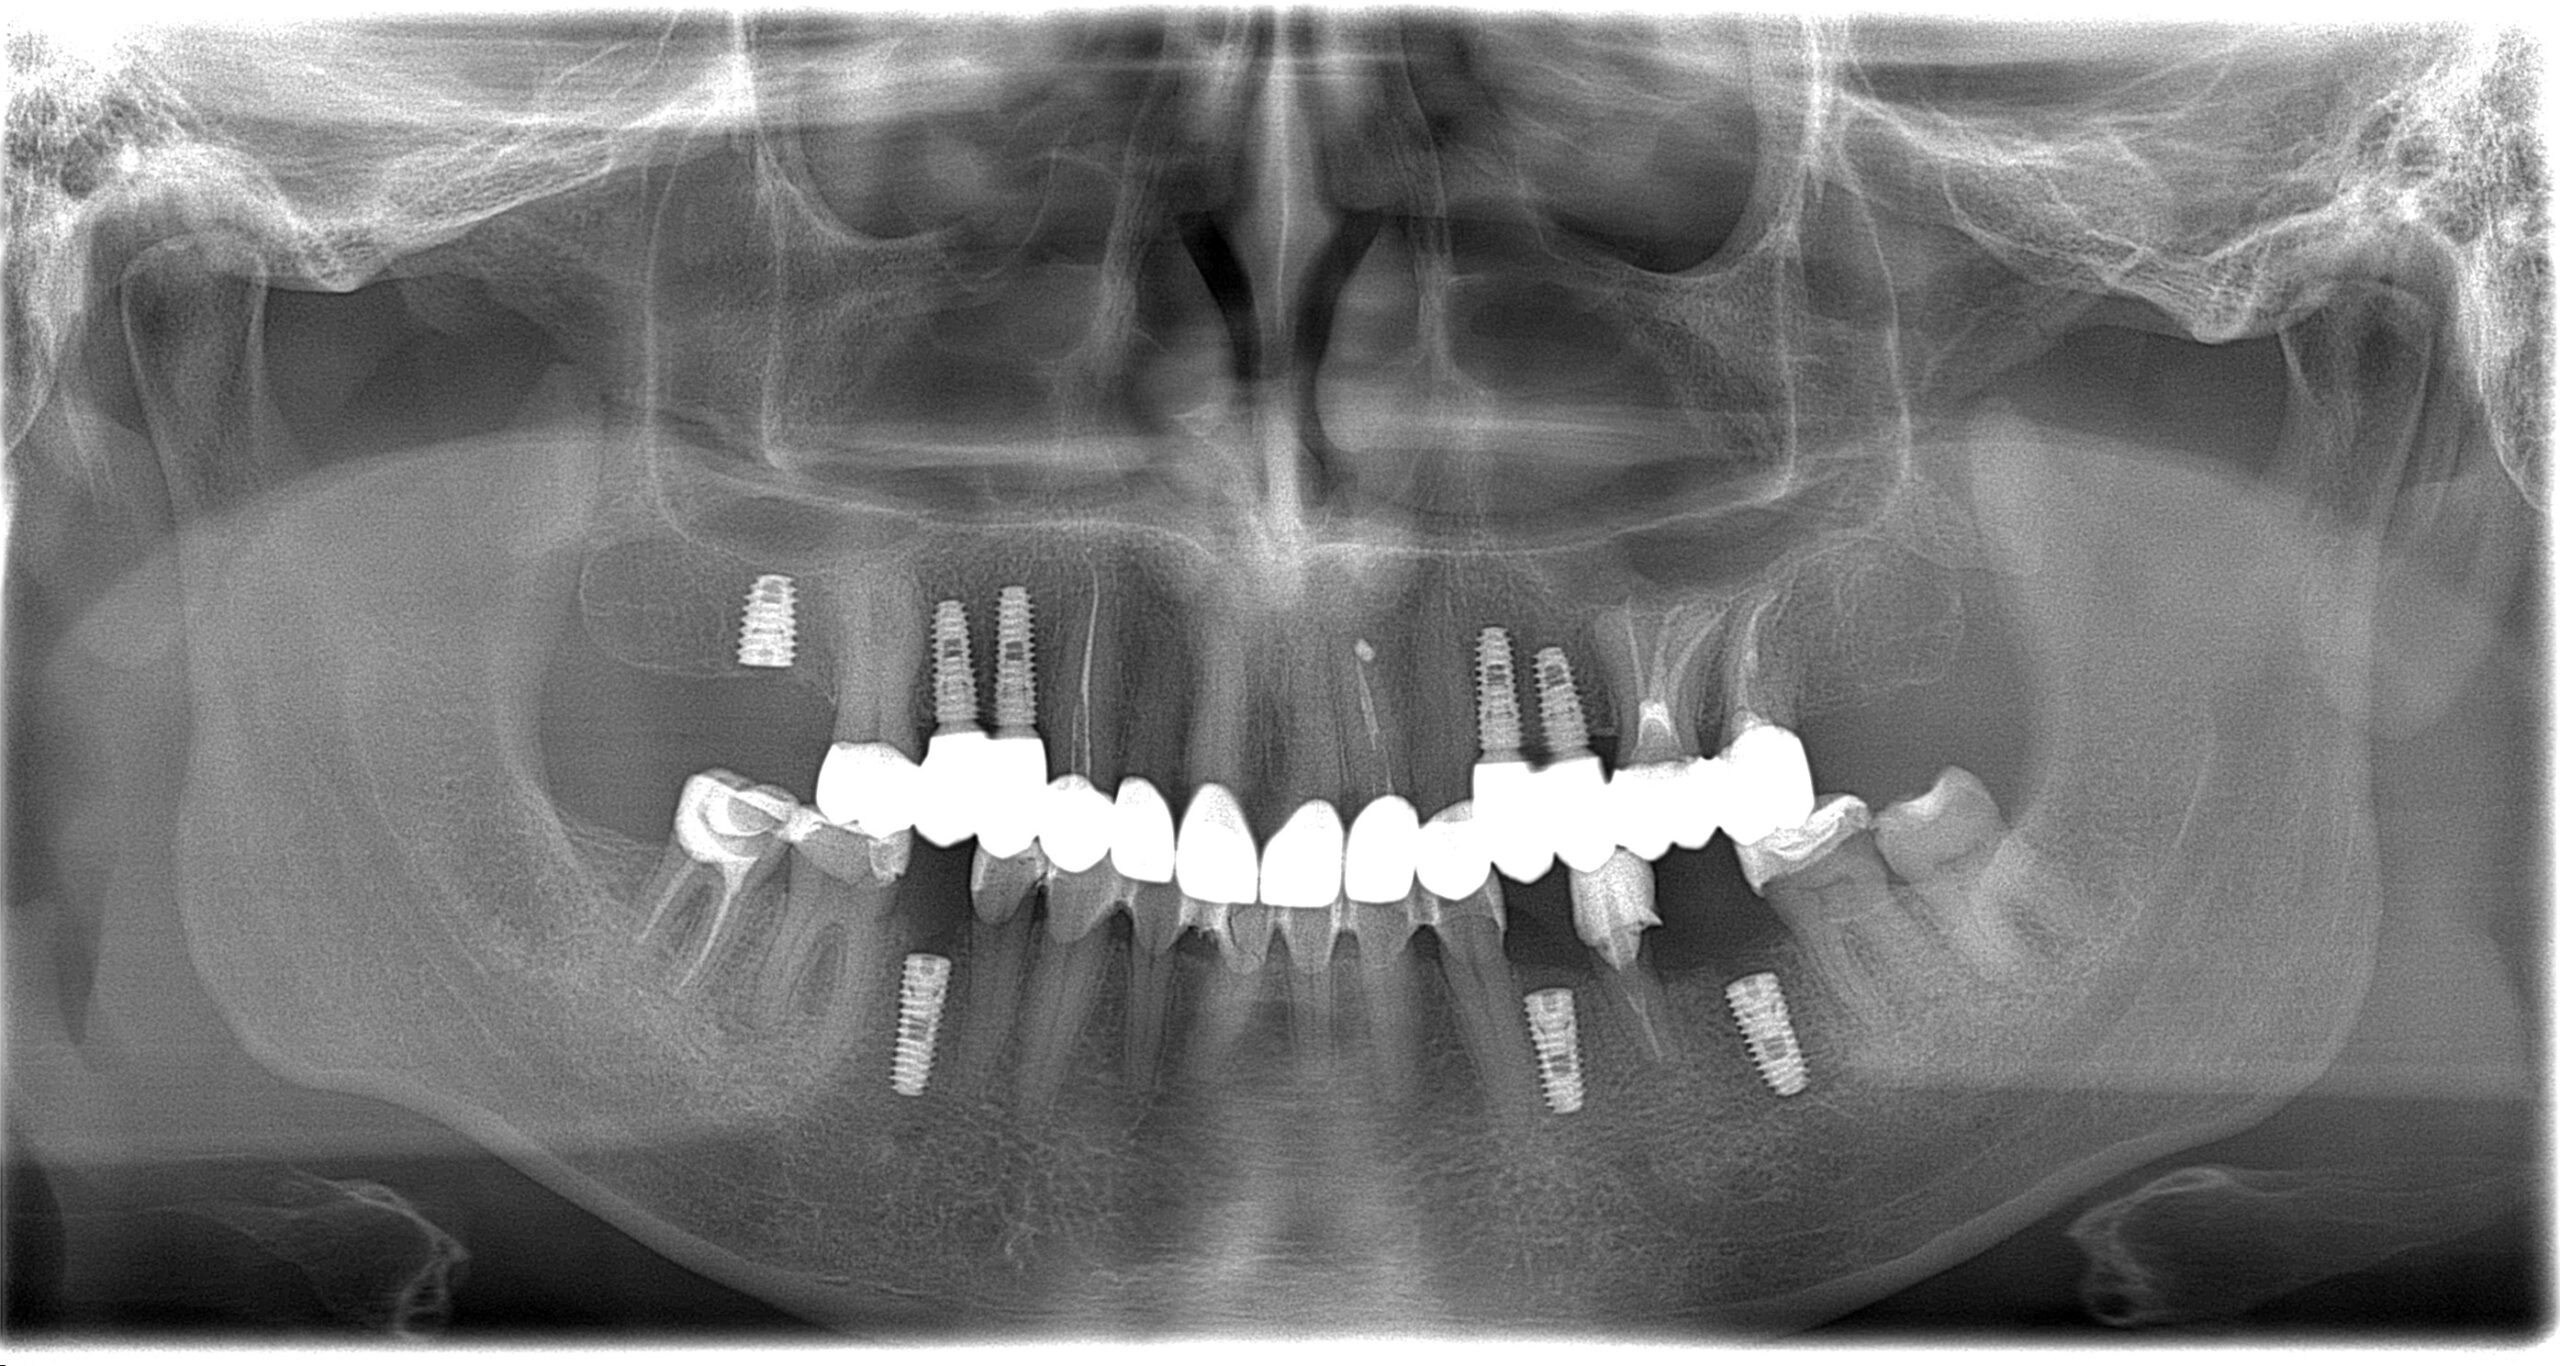

Імплантація